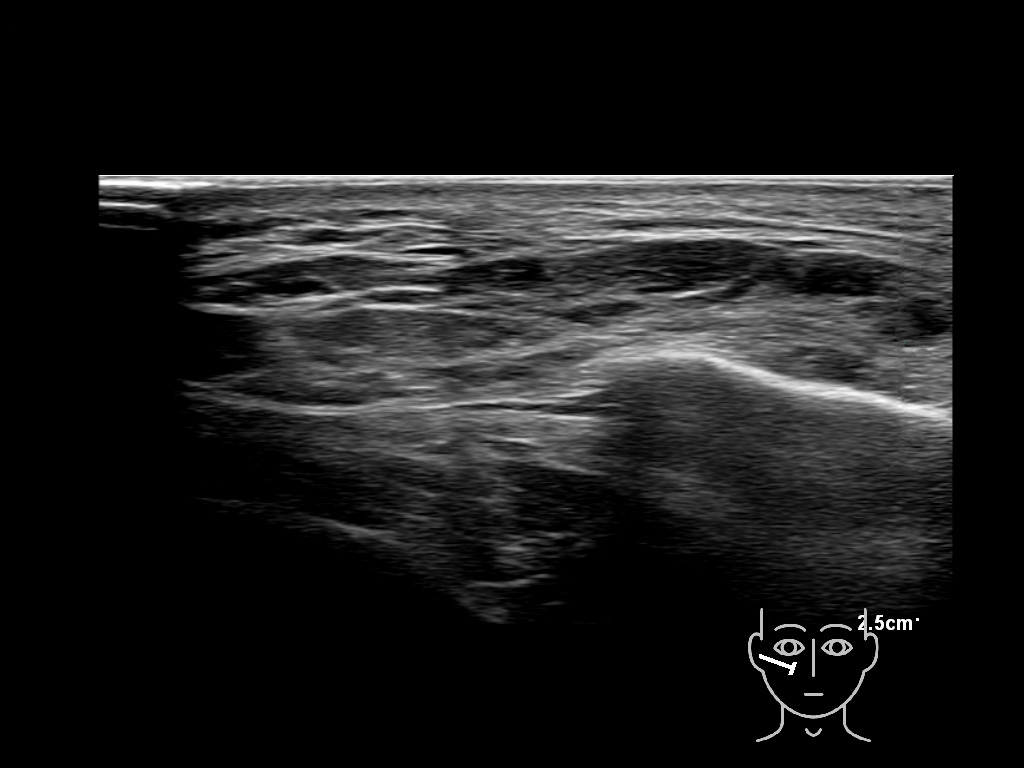

Filler behavior - Temple zygoma US

Study the first image to recognize the different layers. If you are sure about the layers, swipe to the second image to view the answer (if applicable).